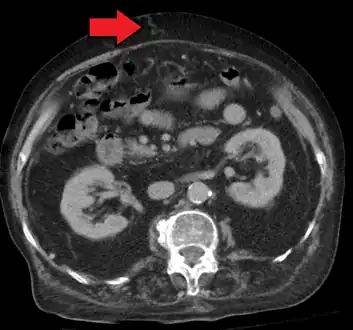

Magnetic resonance imaging of portal hypertension

Portal hypertension due to cirrhosis resulting in revascularization of the umbilical vein

Ultrasonography (US) is the first-line imaging technique for the diagnosis and follow-up of portal hypertension because it is non-invasive, low-cost and can be performed on-site.[12]

A dilated portal vein (diameter of greater than 13 or 15 mm) is a sign of portal hypertension, with a sensitivity estimated at 12.5% or 40%.[13] On Doppler ultrasonography, a slow velocity of <16 cm/s in addition to dilatation in the main portal vein are diagnostic of portal hypertension.[14] Other signs of portal hypertension on ultrasound include a portal flow mean velocity of less than 12 cm/s, porto–systemic collateral veins (patent paraumbilical vein, spleno–renal collaterals and dilated left and short gastric veins), splenomegaly and signs of cirrhosis (including nodularity of the liver surface).[12]